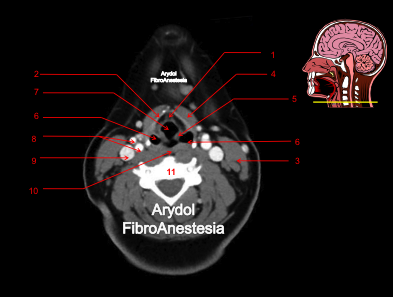

CORTE A NIVEL DEL SUELO DE LA BOCA

1.orofaringe; 2.mandíbula; 3.base de la lengua; 4.suelo de la boca; 5.vena yugular interna; 6.arteria carótida interna; 7.arteria carótida externa